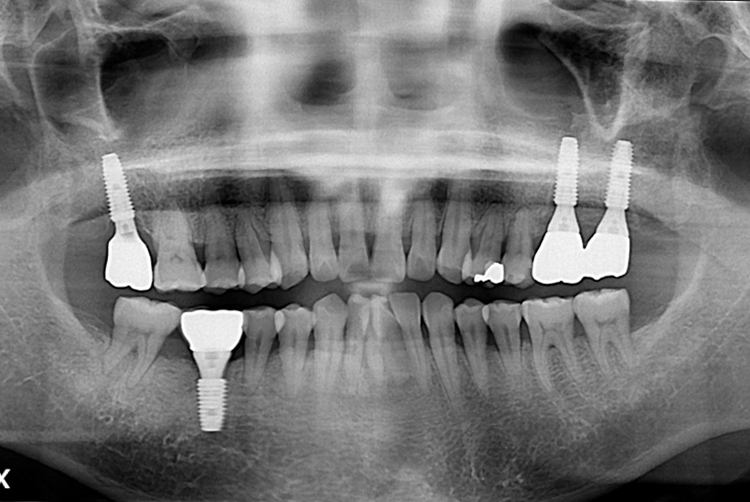

f22d54893eeb107965758cb270f846d7.jpg

치료전 : 2017-06-14